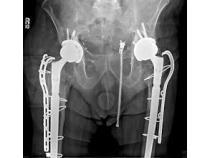

Hip implants are medical devices intended to restore and relieve mobility and relieve pain usually associated with arthritis and hip diseases or injuries. Currently there are five types of total hip replacement available with different bearing surfaces. Metal-on-Polyethylene The ball is made of metal and the socket is made of polyethylene or has a plastic lining. Metal-on-Metal The ball and socket are made of metal. Ceramic-on-Polyethylene The ball is made of ceramic and the socket is made of plastic or has a plastic lining. Ceramic-on-Ceramic The ball is made of ceramic and the socket has a ceramic lining. Ceramic-on-Metal The ball is made of ceramic and the socket has a ceramic lining.